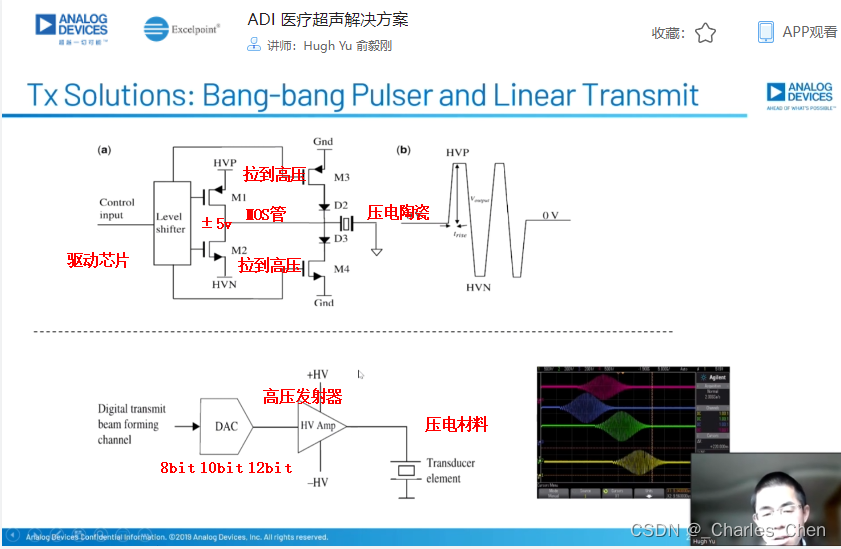

高压发射机

数字发射波束成形器用于产生所要求的数字发射信号,以正确的时间和相位生成聚焦发射信号。高性能超声系统可通过任意波形发生器产生复杂的发射波形,从而优化图像质量。这些情况下,发射波束成形器以大约40MHz速率生成8位至10位数字字符,并以此产生所要求的发射波形。数/模转换器(DAC)将数字波形转换成模拟信号,通过线性高压放大器进行放大,用于驱动传感器单元。由于这种发射技术占用较大体积,而且价格昂贵、需要消耗较高能量,所以,这种架构只限于昂贵的非便携设备。多数超声系统并不使用这种发射波束成形技术,而是采用多级高压脉冲发生器产生需要发射的信号。在这种替代方案中,利用高集成度、高压脉冲发生器快速切换传感器单元至适当的可编程高压电源,产生发射波形。为了产生一个简单的两极发射波形,脉冲发生器需要交替地将传感器单元切换到由数字波束成形器控制的正、负发射电压。更复杂的设计可以让传感器单元切换至多路电源和地,从而产生更复杂、性能更好的多重波形。

近几年,随着二次谐波成像的广泛应用,高压脉冲发生器对于斜率和对称性的要求越来越高。二次谐波成像利用了人体的非线性声学特性。这些非线性特性倾向于将频率fo的声能转变成2fo频率。多种原因使得接收二次谐波信号能够获得更高的图像质量,因此,二次谐波成像得到了广泛应用。

二次谐波成像有两种基本的实现方法。一种称为标准谐波成像,尽可能抑制发射信号的二次谐波,从而使接收到的二次谐波主要源于人体的非线性。这种模式要求二次谐波的发射能量至少低于基波能量50dB。所以,发射脉冲的占空比要求是准确的50%且误差小于±0.2%。另一种方法称为脉冲反相,利用反相后的发射脉冲产生同一图像路径的相位相反的两路接收信号。在接收器中对这两路反相接收信号求和,恢复由于人体非线性产生的谐波信号。这种脉冲反相的方法必须在叠加时尽可能抵消发射脉冲的反相成分。所以,高压脉冲发生器的上升时间和下降时间必须严格一致。

Tx/Rx开关

Tx/Rx开关可以保护低噪声放大器免受高压发射脉冲的影响,同时在接收间歇期间隔离低噪声放大器输入和发射机。该开关一般采用一组正确偏置的二极管阵列实现,当有高压发射脉冲出现时,它们会自动闭合或断开。Tx/Rx开关必须具备很快的恢复时间,以保证接收机在发射一个脉冲后能够立刻开启。这些快速恢复时间对于浅埋成像和提供低导通电阻确保接收灵敏度至关重要。